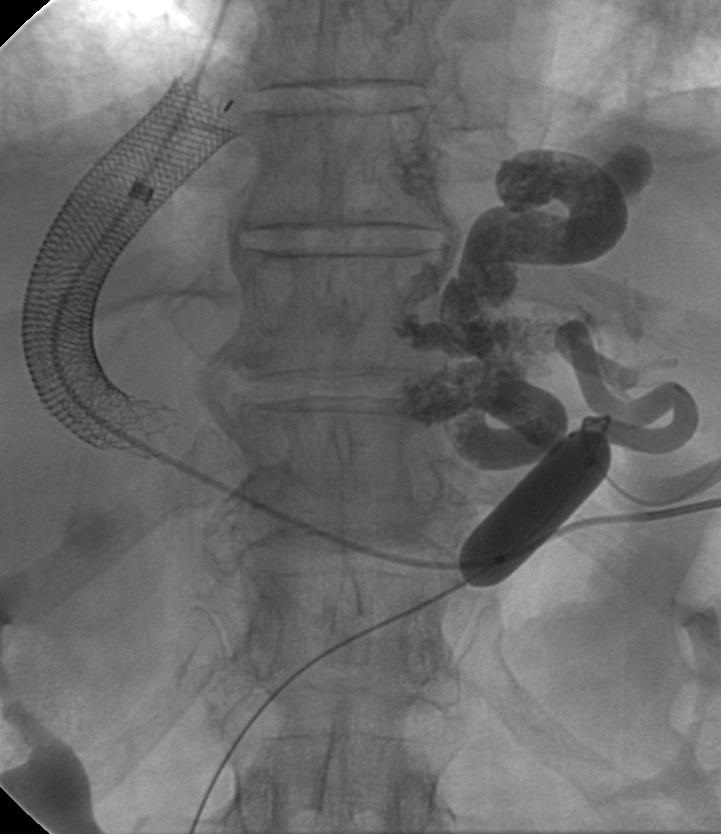

Lenhart 等人报告Onyx胶用于消化道出血的栓塞,2个中心共16例病人,其中6例为典型的消化道出血,其它为假性动脉瘤,创伤和肿瘤[7]。 ![]() 消化道出血栓塞剂选择的结论 1. 第一选择 = 弹簧栓子,但要检查是否“后门”开放 2. 第二选择 = PVA(200μm, 低剂量 0.1-0.5 cc 3. 最后的选择 = 胶,如果是仅有的选择,或关闭“后门”/ 特殊的病例,和血流控制 4. 经验栓塞: 弹簧栓子+明教海绵 1. Bertrand Janne d’Othée et al, Cardiovasc Intervent Radiol 2006: 49-58 2. Aina R, Oliva VL, Therasse E, Perreault P, Bui BT, Dufresne MP, Soulez G. Arterial embolotherapy for upper gastrointestinal hemorrhage: outcome assessment. J Vasc Interv Radiol. 2001 Feb;12(2):195-200. 3. Loffroy R, Guiu B, D'Athis P, Mezzetta L, Gagnaire A, Jouve JL, Ortega-Deballon P, Cheynel N, Cercueil JP, Krausé D. Arterial embolotherapy for endoscopically unmanageable acute gastroduodenal hemorrhage: predictors of early rebleeding. Clin Gastroenterol Hepatol. 2009 May;7(5):515-23. 4. Yap FY, Omene BO, Patel MN, Yohannan T, Minocha J, Knuttinen MG, Owens CA, Bui JT, Gaba RC. Transcatheter embolotherapy for gastrointestinal bleeding: a single center review of safety, efficacy, and clinical outcomes. Dig Dis Sci. 2013 Jul;58(7):1976-84. 5. Frodsham A, Berkmen T, Ananian C, Fung A. Initial experience using N-butyl cyanoacrylate for embolization of lower gastrointestinal hemorrhage. J Vasc Interv Radiol. 2009 Oct;20(10):1312-9. 6. Huang CC, Lee CW, Hsiao JK, Leung PC, Liu KL, Tsang YM, Liu HM. N-butyl cyanoacrylate embolization as the primary treatment of acute hemodynamically unstable lower gastrointestinal hemorrhage. J Vasc Interv Radiol. 2011 Nov;22(11):1594-9. 7. Lenhart M, Paetzel C, Sackmann M, Schneider H, Jung EM, Schreyer AG, Feuerbach S, Zorger N. Superselective arterial embolisation with a liquid polyvinyl alcohol copolymer in patients with acute gastrointestinal haemorrhage.Eur Radiol. 2010 Aug;20(8):1994-9. 8. Encarnacion CE, Kadir S, Beam CA, Payne CS. Gastrointestinal bleeding: treatment with gastrointestinal arterial embolization. Radiology. 1992 May;183(2):505-8. 9. Jae HJ, Chung JW, Jung AY, Lee W, Park JH. Transcatheter arterial embolization of nonvariceal upper gastrointestinal bleeding with N-butyl cyanoacrylate. Korean J Radiol. 2007 Jan-Feb;8(1):48-56. | |||||||||||||||||||||||||||||||||||||||||||||||||||||||||||||||||||||||||||||||||||||||||||||||||||||||||||||||||||||